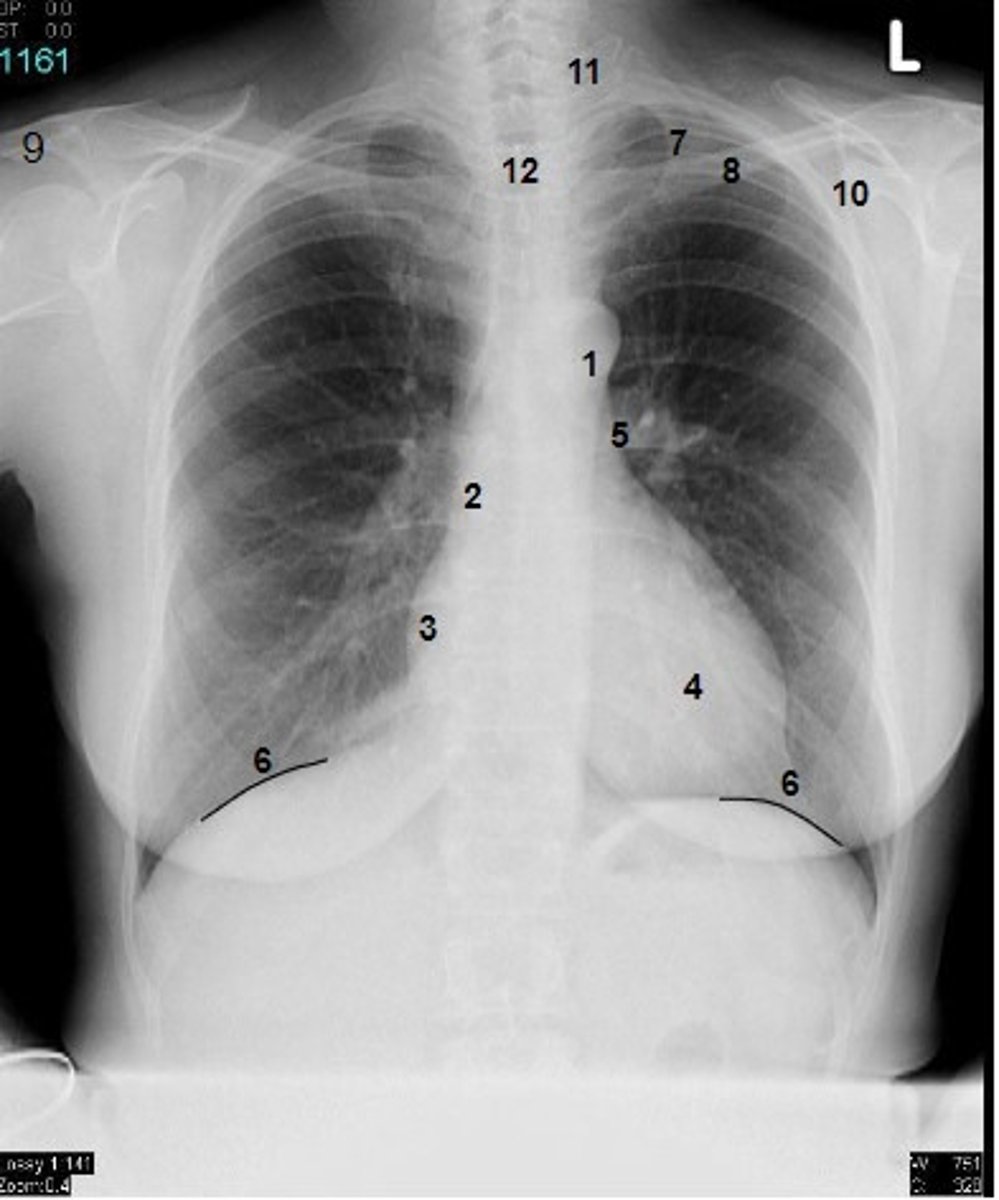

1

at what number is the arch of aorta?

2

at what number is the superior vena cava

3

at what number is the right atrium

4

at what number is the left ventricle

5

at what number is the primary bronchus

6

at what number is the dome of diaphragm

7

at what number is the first rib

8

at what number is the clavicle

9

at what number is the acromion of scapula

10

at what number is the coracoid process of scapula

11

at what number is the transverse process of vertebra

12

at what number is the spinous process of vertebra